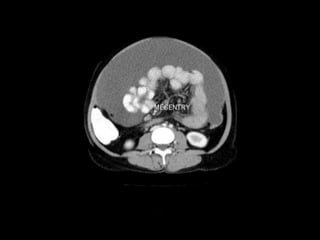

Mesenteries True mesenteries allconnect to the posterior peritoneal wall. These are: The small bowel mesentery The transverse mesocolon The sigmoid mesentery (or mesosigmoid) Specialized mesenteries do not connect to the posterior peritoneal wall. These are: The greater omentum: connects the stomach to the colon The lesser omentum: connects the stomach to the liver The mesoappendix: connects the appendix to the ileum

1-The lesser omentum 2-Transverse mesocolon 3-Smallbowel mesentery 4-Sigmoid mesentery Mesenteries